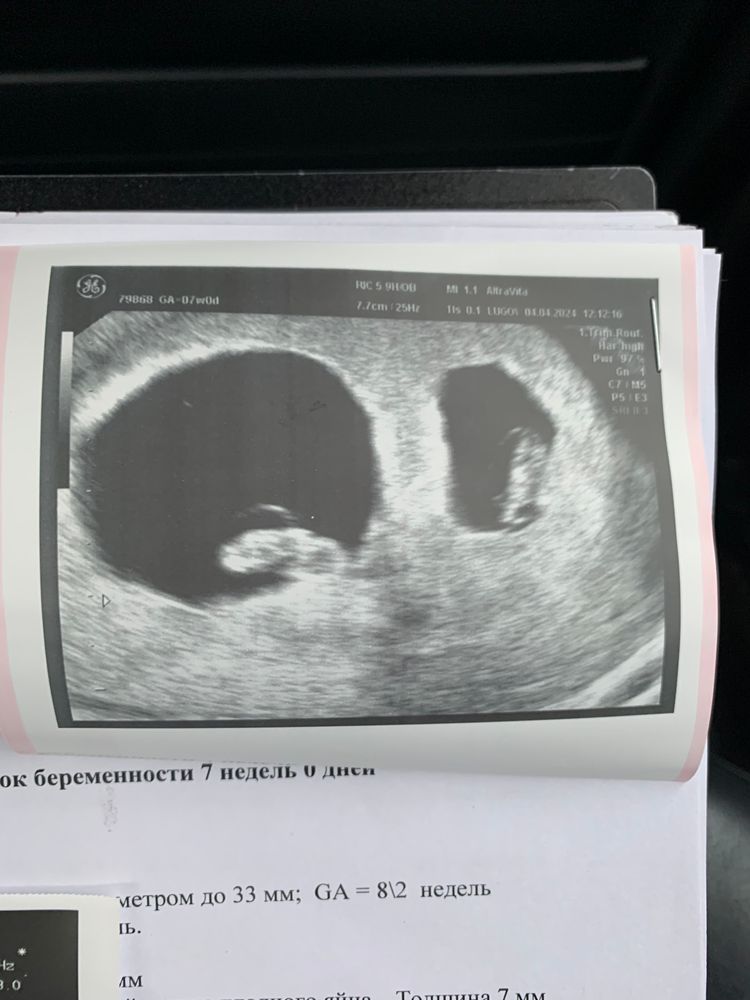

Сегодня ровно месяц со дня переноса,31 дпп. Я увидела своих малышей,послушала их сердечки 💕ктр у обоих малышей 10 мм,что соответствует сроку беременности,пя у одного малыша побольше,чем у другого,но врач сказал,что это нормально. ЧСС у одного 140 ударов,у другого 133 удара. До сих пор не верится,что я снова беременна. Девочки,милые,желаю каждой из вас испытать это счастье❤️Не опускайте руки,помните,что с каждым днем вы все ближе к своей мечте ❤️